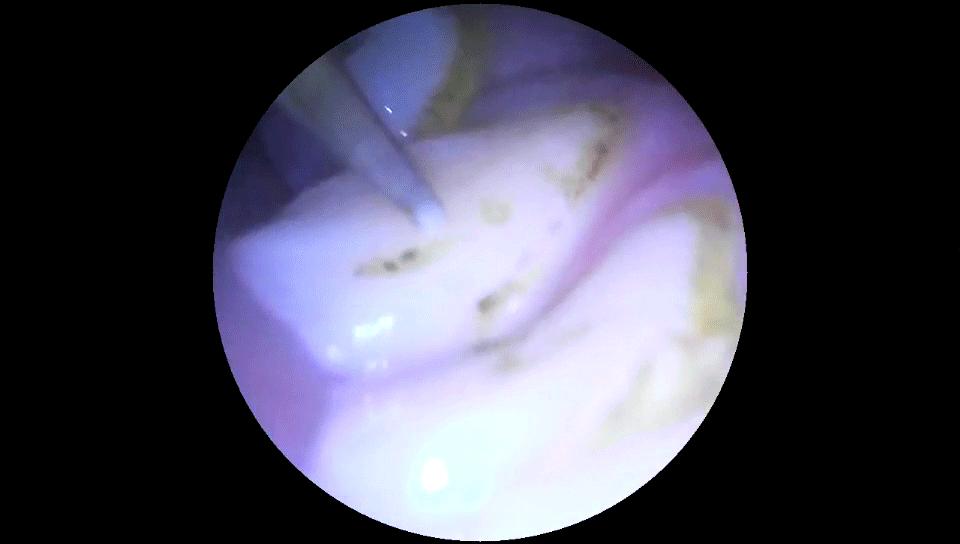

使用体验方面,素诺T11Pro接触到牙齿后能够听到"滋滋"的声音,同时牙齿也能感觉到轻微的震感,没有产生不适感。并且,当工作尖碰到牙龈后,洁牙仪会停止振动,安全性能非常优秀。结合下面的视频可以看到,素诺T11Pro很轻松地就清洁掉了牙齿表面上的牙渍和结石,清洁效果非常不错。

通过下面的对比照片可以看到,在经过一番"清理"之后,附着在我牙齿上的牙结石已经被清洁了下来,素诺T11Pro的清洁效果可以说非常明显。